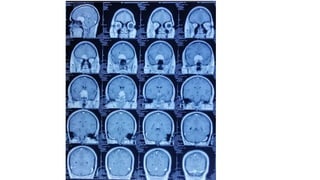

Radiological findings

• Multiplaner sagital ,coronal and axial images show a well defined ,midline, broad dural based,

lobulated T1WI iso , T2WI iso to slightly hyper and FlAIR hyperintense mass noted in suprasellar

Radiological findings • Multiplanersagital ,coronal and axial images show a well defined ,midline, broad dural based, lobulated T1WI iso , T2WI iso to slightly hyper and FlAIR hyperintense mass noted in suprasellar area having extension forwards along the planum sphenoidale and backwards along the dorsum sellae. • After IV contrast avidly homogenous enhancement of the lesion and adjacent linear dural enhancement over the clivus and planum sphenoidale representing dural tail are noted. • The lesion causing compression over the optic chiasma, pituitary gland and floor of 3rd ventricle, and encasing the supraclinoid ICA, ACA and MCA of both sides. • The mass effect is evidenced by obliteration of Suprasellar & interpeduncular cysterns and symmetrical indentation of underlying cerebral cortex. • No perilsional edema is noted • However lateral , 3rd and 4rth ventricles appear normal • Complementary CT cut was taken and showing iso to slightly hyperdense lesion. No calcification is noted. Bone CT shows bony hyperostosis at planum sphenoidale .Sellar size is within normal limit

Radiological diagnosis • Suprasellarmeningioma with planum sphenonale and dorsum sallar extension